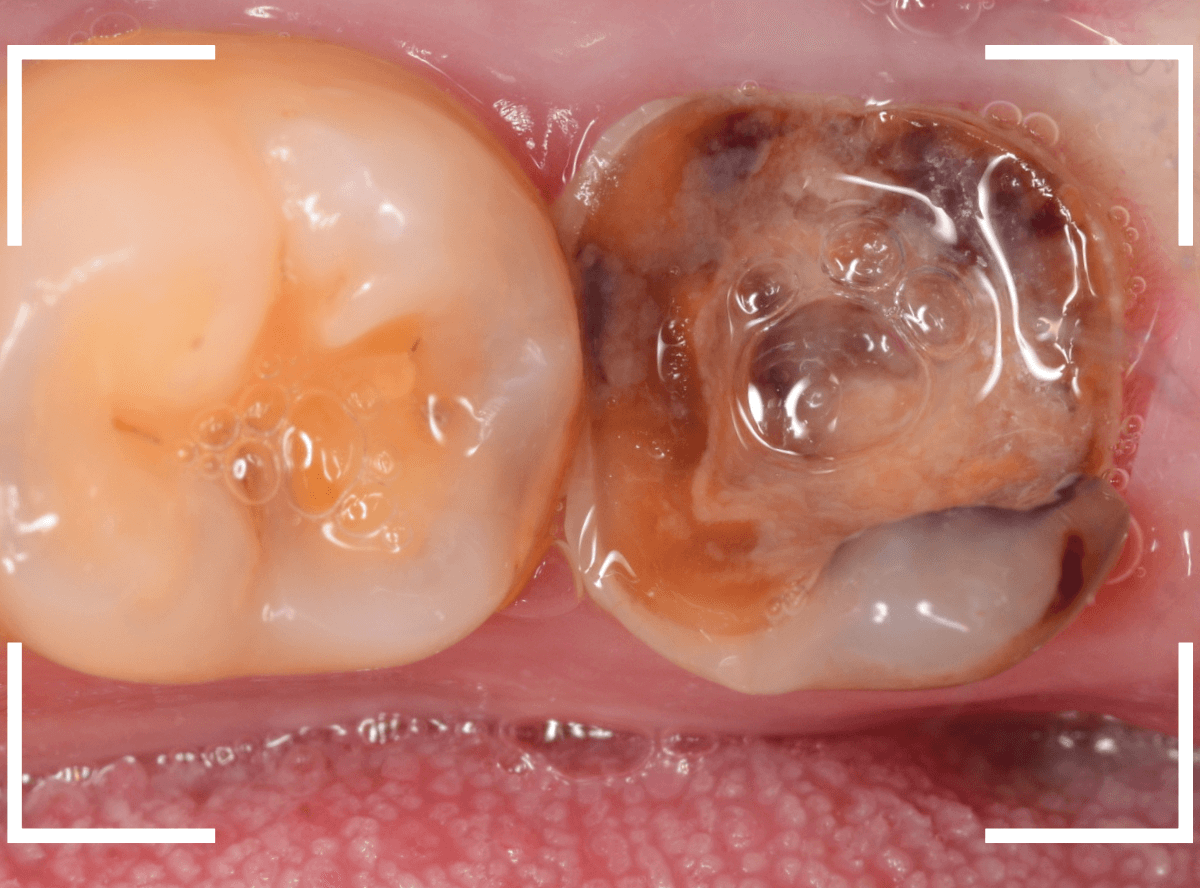

抜歯後に長期間お痛みが出たり、経過観察が必要な難しいおやしらずの抜歯ならまだしも、簡単なおやしらずの抜歯を避けてしまったがために、他の歯に悪影響を与えてしまったもったいない例も多々見てきました。

ここでは、比較的簡単なおやしらずの抜歯の例を中心にご紹介します。

このようなおやしらず、あなたはありませんか?